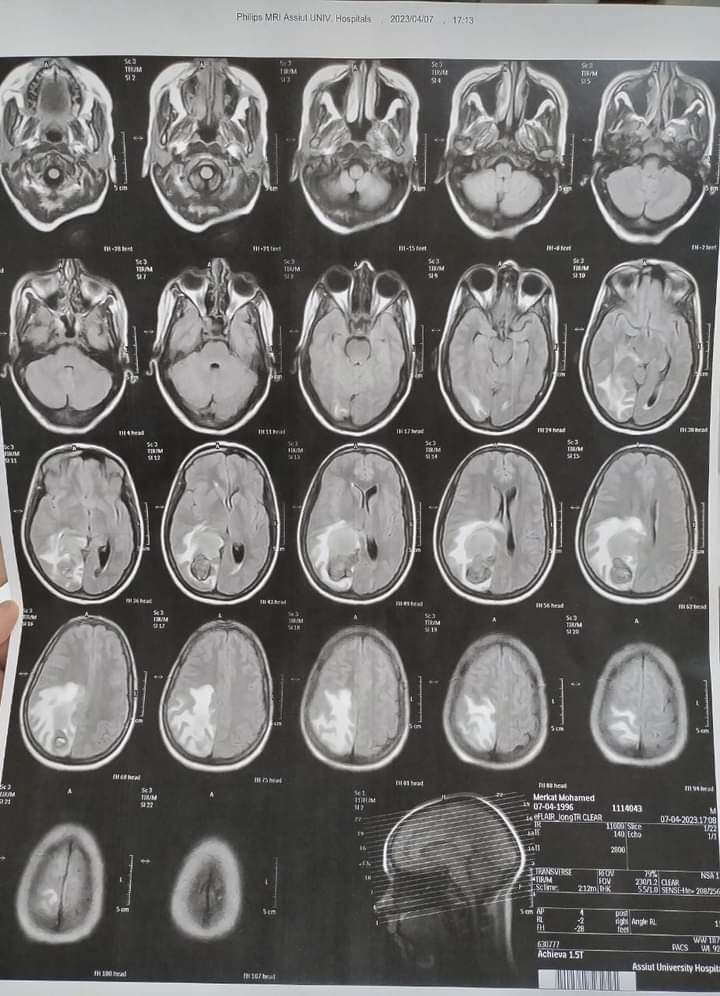

أجرى الفريق الطبي بنجاح جراحة لمريضة عمرها 28 عاما تعاني من صداع مستمر، وبمناظرة الأشعات تبين وجود وحمة دموية كبيرة نافذة ضاغطة على مركز الحركة، وعلى الفور تشكل قام الفريق الطبي بقيادة الدكتور محمد عبد الباسط خلاف رئيس قسم جراحة المخ والأعصاب ومدير المستشفى، يعاونه الدكتور محمد سيد عبد العال مدرس التخدير والعناية المركزة، والطبيب مصطفى كاشف مدرس مساعد جراحة المخ والأعصاب، وتم إجراء الجراحة و استئصال كامل للوحمة الدموية، بواسطة الميكروسكوب الجراحي وجهاز الأشعة التليفزيونية على المخ مع الحفاظ على جميع المراكز الحساسة بالمخ.